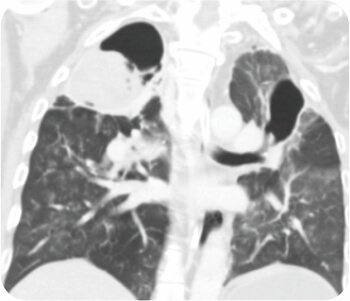

CT chest was suggestive of cavity in left upper lobe. FOB was suggestive of pus oozing from left upper lobe bronchus with a clot mass adherent to left upper lobe bronchus. Subsequent bronchoalveolar lavage was predominantly neutrophilic. Staining and culture for pyogenic, fungus, tuberculosis and nocardia was negative. Cytology was negative for malignancy. A diagnosis of Invasive Mucormycosis was made.

CT chest – cavity in left upper lobe